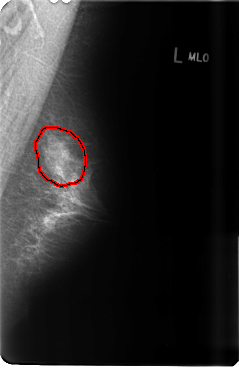

B_3479_1.LEFT_MLO

FILE: B_3479_1.LEFT_MLO.OVERLAY

TOTAL_ABNORMALITIES 1

ABNORMALITY 1

LESION_TYPE CALCIFICATION TYPE PUNCTATE DISTRIBUTION SEGMENTAL

ASSESSMENT 4

SUBTLETY 3

PATHOLOGY BENIGN

TOTAL_OUTLINES 1

BOUNDARY